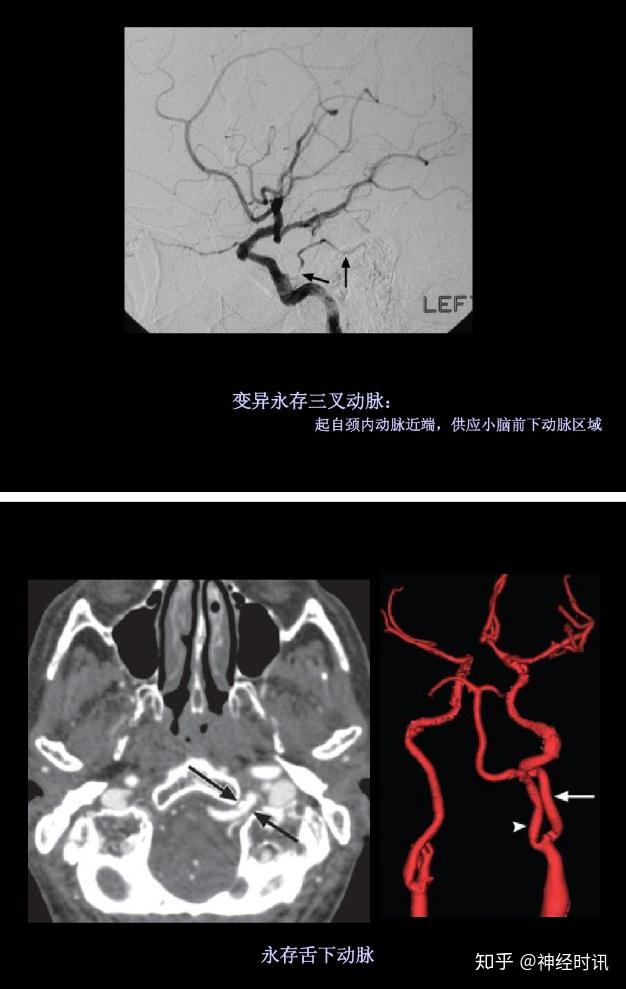

病例结果:永存三叉动脉编辑/校对:郑孝飞ct女,63岁,因"头晕20天"入院

少见血管变异永存三叉动脉3例

相反,永存舌下动脉代表椎动脉发育不全,其作用由咽升动脉神经脑膜干的

左侧永存舌下动脉和颈内动脉闭塞.